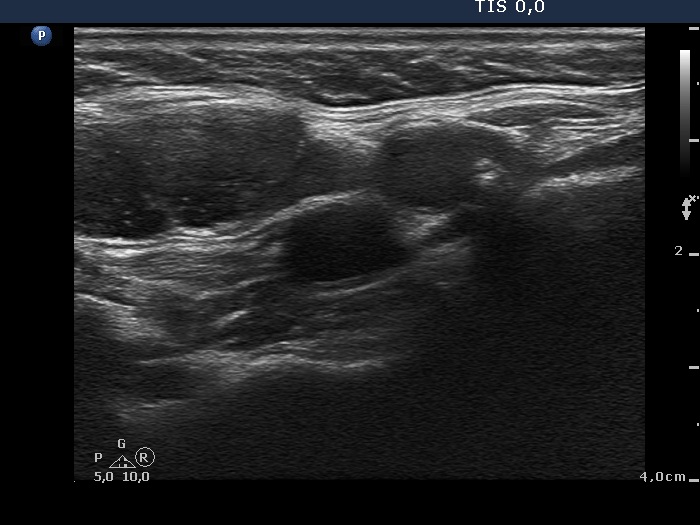

Lymph nodes in the neck - Case 674 (ultrasonographic picture 10)

Right submandibular area, longtudinal scan. The tumorous node left in the image while a reactive-type lymph node right in the image.